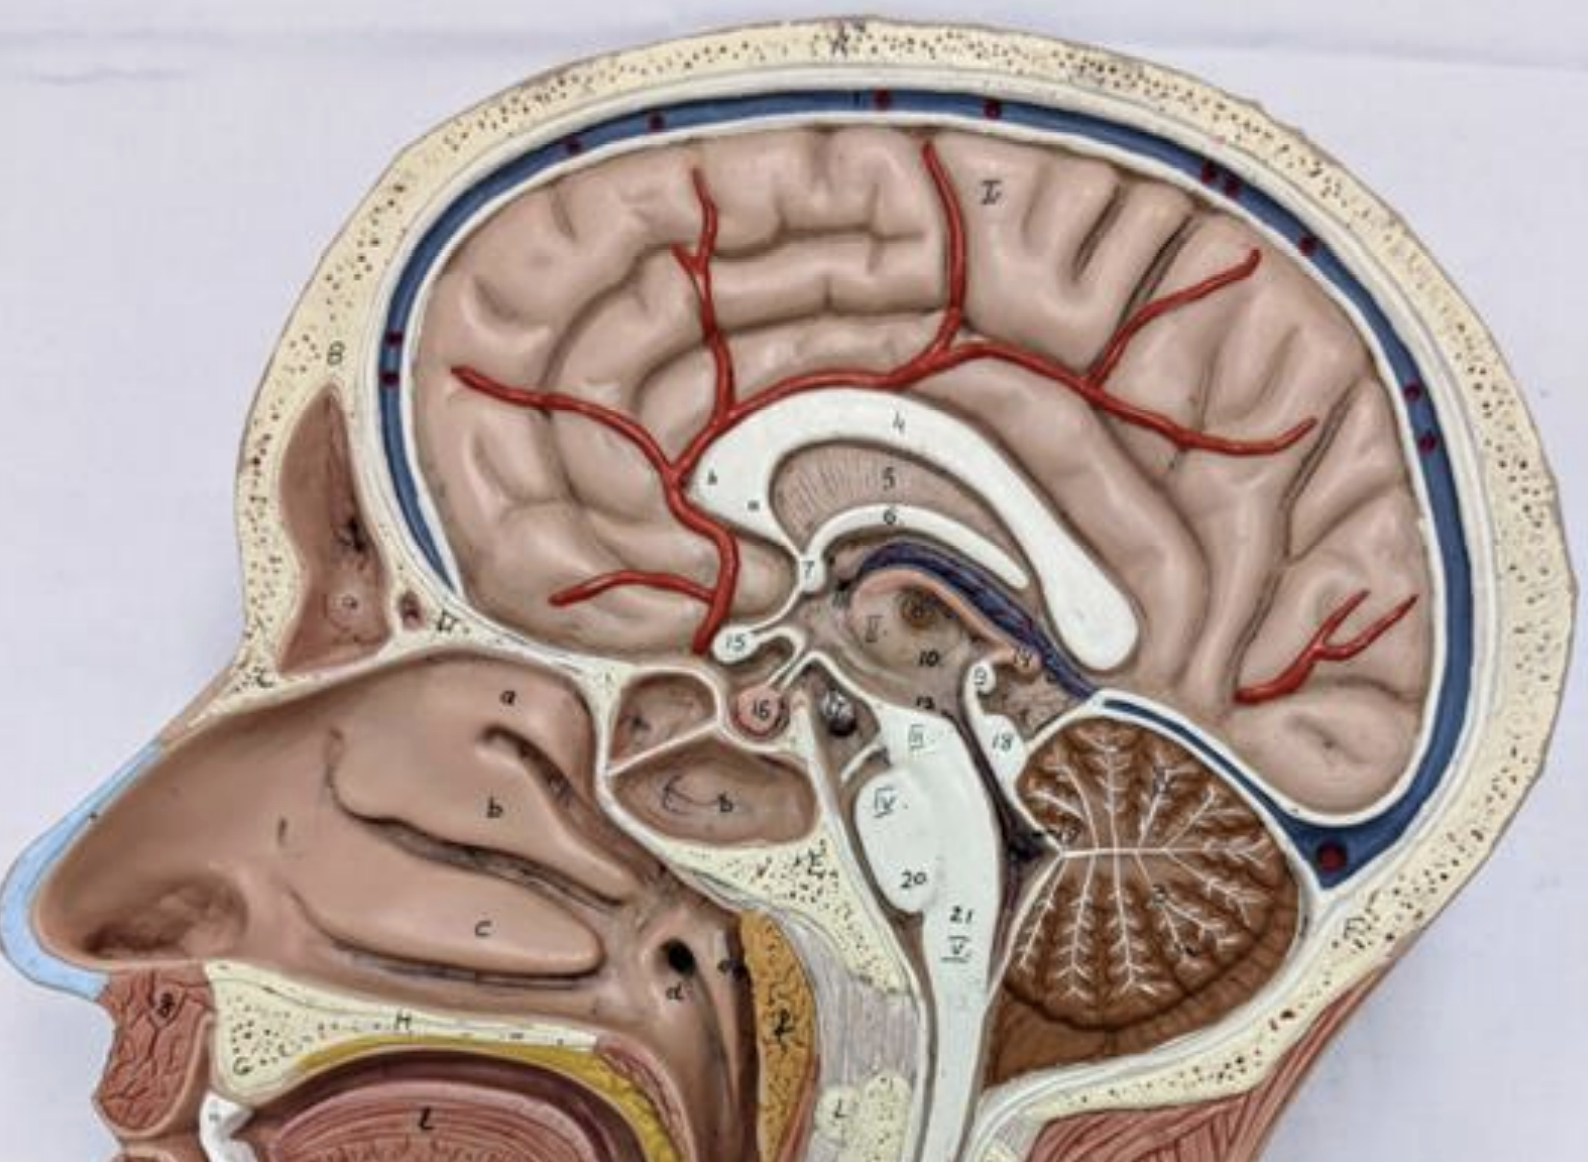

The lateral ventricle:

Anterior (frontal) horn

Body

Posterior (occipital) horn

Inferior (temporal) horn

Interventricular foramen

Foramen for the interthalamic mass

Third ventricle

Cerebral aqueduct

Fourth ventricle

Medial and lateral foramen

Central canal

Flow of CSF

Cranial Dural Folds

Falx cerebri

Tentorium cerebelli

Falx cerebelli.

Circle of Willis

Superior sagittal sinus

Straight sinus

Confluence of sinuses

Transverse sinuses

Sigmoid sinuses

Cavernous sinuses

Intercavernous sinus

Superior petrosal sinuses/inferior petrosal sinuses

Occipital sinus

Sphenoparietal sinuses